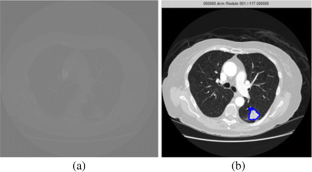

Fig. 2